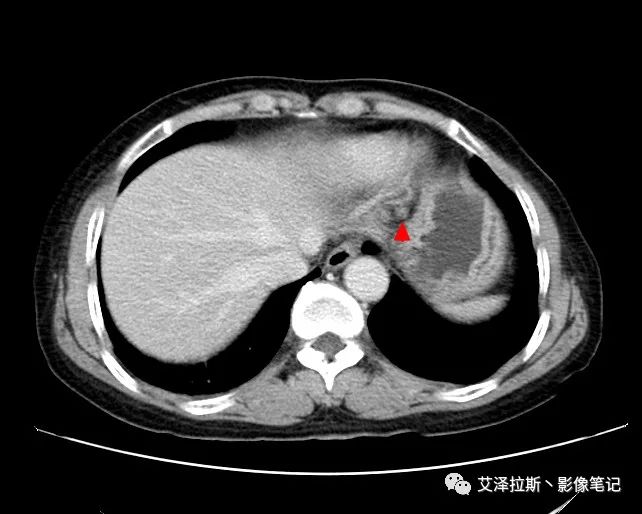

【影像所见】 胃窦部狭窄,胃壁环形增厚,小弯侧见一巨大溃疡,周围伴“环堤征”,浆膜面不完整,胃周脂肪见网格状条索影,病灶与肝脏左叶、胰腺钩突脂肪间隙消失,增强扫描病灶明显强化。引流区内约15个区域淋巴结受累。

【诊断意见】 胃窦部胃癌(T4N3期) 该病例肿块突破浆膜层,与肝脏左叶、胰腺钩突分界不清,脂肪界面消失,定为T4期; 受累及的淋巴结为15个区域,定为N3; 有无远处转移尚不明确,所以M期暂时无法确定。